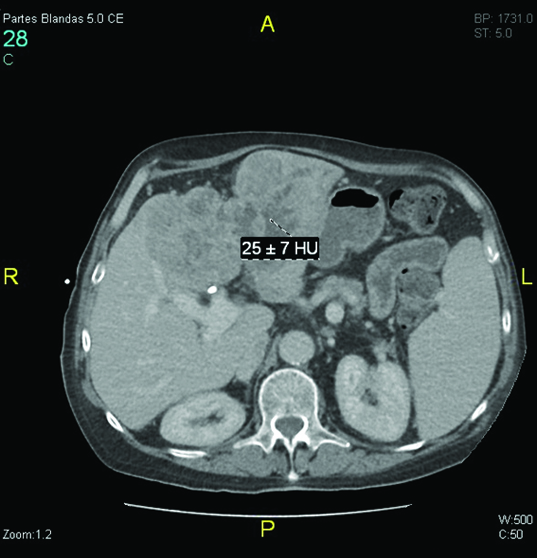

Percutaneous transhepatic cholangiography was then performed after ciprofloxacin prophylaxis. Internal-external drainage was placed during the intervention. During the procedure, solid material occupying the bile duct was unexpectedly identified [Table/Fig-1]. Pathological analysis demonstrated the presence of solid tumour fragments of adenocarcinoma [Table/Fig-2]. At this time, microbiological study of biliary fluid did not detect bacterial cholangitis. Given these findings, abdominal CT images were reviewed which revealed increased iodinated contrast uptake within the dilated bile duct, suggestive of bile duct tumour invasion [Table/Fig-3].

Abdominal computed tomography (CT). A contrast enhanced CT scan demonstrated dilatation of the intra- and extrahepatic bile duct and increased uptake of iodinated contrast within the dilated bile duct, suggestive of bile duct tumour invasion.